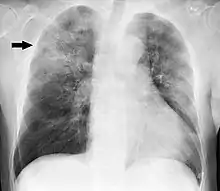

A chest X-ray showing a very prominent wedge-shaped area of airspace consolidation in the right lung characteristic of acute bacterial lobar pneumonia

A black-and-white image shows the internal organs in cross-section as generated by CT. Where one would expect black on the left, one sees a whiter area with black sticks through it.

CT of the chest demonstrating right-sided pneumonia (left side of the image)

A chest radiograph is frequently used in diagnosis.[23] In people with mild disease, imaging is needed only in those with potential complications, those not having improved with treatment, or those in which the cause is uncertain.[23][67] If a person is sufficiently sick to require hospitalization, a chest radiograph is recommended.[67] Findings do not always match the severity of disease and do not reliably separate between bacterial and viral infection.[23]

X-ray presentations of pneumonia may be classified as lobar pneumonia, bronchopneumonia, lobular pneumonia, and interstitial pneumonia.[73] Bacterial, community-acquired pneumonia classically show lung consolidation of one lung segmental lobe, which is known as lobar pneumonia.[41] However, findings may vary, and other patterns are common in other types of pneumonia.[41] Aspiration pneumonia may present with bilateral opacities primarily in the bases of the lungs and on the right side.[41] Radiographs of viral pneumonia may appear normal, appear hyper-inflated, have bilateral patchy areas, or present similar to bacterial pneumonia with lobar consolidation.[41] Radiologic findings may not be present in the early stages of the disease, especially in the presence of dehydration, or may be difficult to interpret in the obese or those with a history of lung disease.[24] Complications such as pleural effusion may also be found on chest radiographs. Laterolateral chest radiographs can increase the diagnostic accuracy of lung consolidation and pleural effusion.[40]